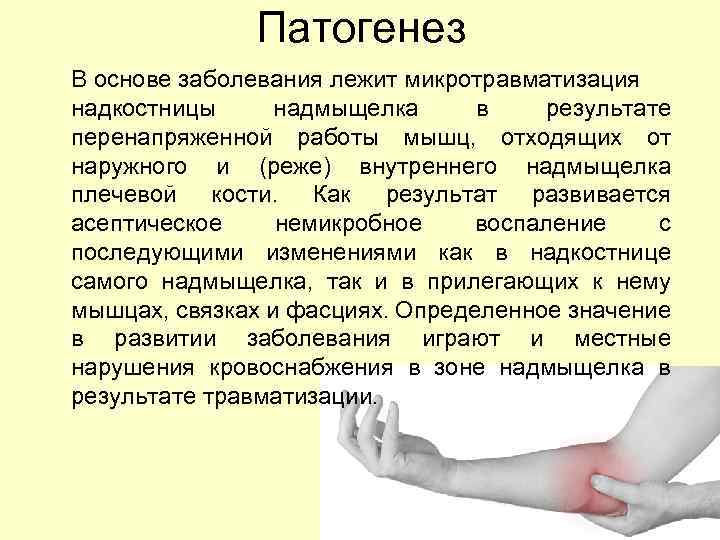

Патогенез В основе заболевания лежит микротравматизация надкостницы надмыщелка в результате перенапряженной работы мышц, отходящих от наружного и (реже) внутреннего надмыщелка плечевой кости. Как результат развивается асептическое немикробное воспаление с последующими изменениями как в надкостнице самого надмыщелка, так и в прилегающих к нему мышцах, связках и фасциях. Определенное значение в развитии заболевания играют и местные нарушения кровоснабжения в зоне надмыщелка в результате травматизации.